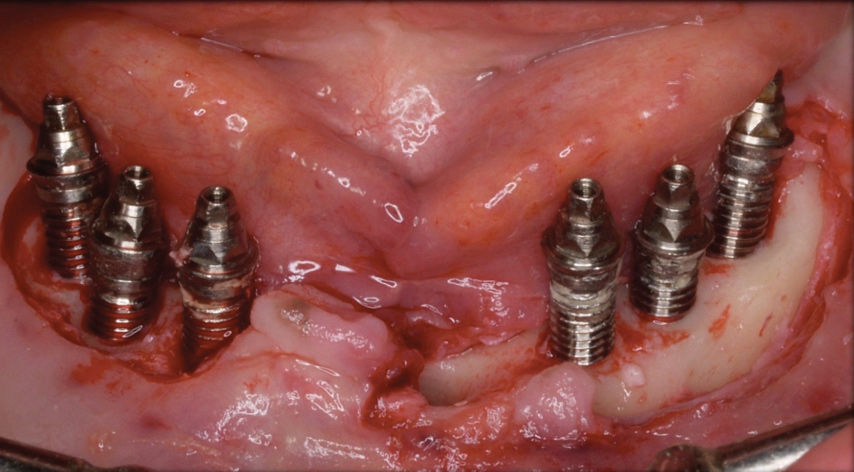

Fig 15. Access flaps to allow mechanical debridement of implant surfaces.

Figure 15

Following a similar paradigm of treating peri-implantitis the same way that periodontitis is regularly successfully treated, based on the mechanical removal of biofilms adhered to implant/abutment surfaces, different protocols of nonsurgical implant debridement using different mechanical, physical, and chemical mechanisms have been evaluated (Figure 12 through Figure 15). In general, the use of different protocols combining treatments aimed to decontaminate the implant surface (eg, mechanical, lasers) and control the infection process (eg, antiseptics, antibiotics) have shown clinical and significant improvements in the commonly used surrogate outcomes (mean reductions in PPD of around 1.2 mm and mean reductions in the scores of BOP of about 50%) but have not resulted in disease resolution18 or a high degree of predictablility.19 There is currently no specific nonsurgical therapy that has shown efficacy in the resolution of peri-implantitis, and the clinical improvements reported in the clinical studies were not sufficient for the arrest of the disease, leaving the standard of care in the treatment of peri-implantitis as surgical in most cases.20